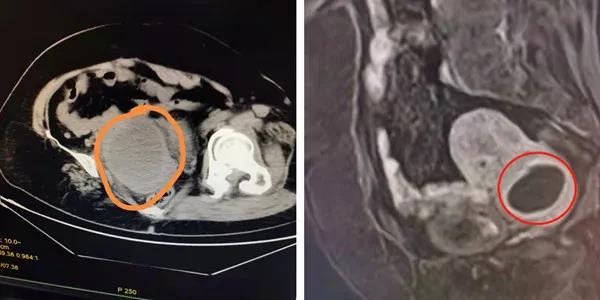

7月11日,患者张阿姨初至某三甲幸运轮盘 急诊就诊,查CT提示子宫体积明显增大,可见10*6.9cm类圆形低密度影,查彩超却提示左附件区低回声74*71mm,与子宫分界不清。住院抗炎治疗半个月,出院前复查彩超,仍提示包块位于左附件处。但是当张阿姨于一个月后来到幸运轮盘娱乐中心 再复查阴道彩超时,结果又提示子宫下段囊性包块,直径约4cm。通俗来说,就是初诊时CT提示“异物”在子宫腔内,彩超提示“异物”在子宫外围附件上,而一个月之后幸运轮盘娱乐中心 复查阴道彩超又提示“异物”到了子宫颈处。这到处“移动”的盆腔肿物,实在不常见,为进一步诊治,顾爱玲主任将张阿姨收住了院。

入院后,为进一步确认张阿姨的情况,行盆腔增强磁共振,提示:子宫下段宫颈前壁肌层内病灶,约4公分,不排除脓肿。完善各项术前检查,顾爱玲主任诊查病人后分析:患者发病已有一月,起病有发热、外院抗感染治疗有效,考虑盆腔感染明确。但几次检查结果均不一致,这移动的、会跑的盆腔包块,究竟是什么?实属罕见!

△图左:查急诊CT提示宫腔内病灶

△图右:增强磁共振MRI提示宫颈肌层内病灶